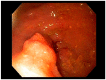

Gastric and esophageal tumors are diverse neoplasms that involve mucosal and submucosal tissue layers and include squamous cell carcinomas, adenocarcinomas, spindle cell neoplasms, neuroendocrine tumors, marginal B cell lymphomas, along with less common tumors. The worldwide burden of esophageal and gastric malignancies is significant, with esophageal and gastric cancer representing the ninth and fifth most common cancers, respectively. The approach to diagnosis and staging of these lesions is multimodal and includes a combination of gastrointestinal endoscopy, endoscopic ultrasound, and cross-sectional imaging. Likewise, therapy is multidisciplinary and combines therapeutic endoscopy, surgery, radiotherapy, and systemic chemotherapeutic tools. Future directions for diagnosis of esophageal and gastric malignancies are evolving rapidly and will involve advances in endoscopic and endosonographic techniques including tethered capsules, optical coherence tomography, along with targeted cytologic and serological analyses.